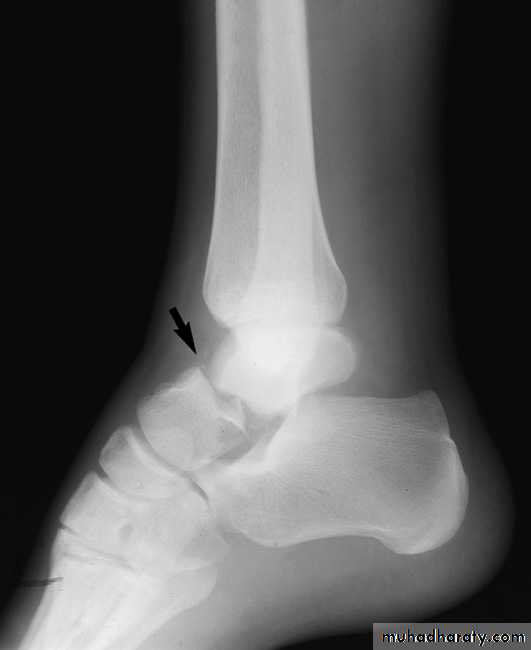

Fracture Talus: A talus fracture is a break in one of the bones that forms the ankle. This type of fracture often occurs during a high-energy event, such as a car collision or a high-velocity fall. Because the talus is important for ankle movement, a fracture often results in significant loss of motion and function. In addition, a talus fracture that does not heal properly can lead to serious complications, including chronic pain. For this reason, many talus fractures require surgery.